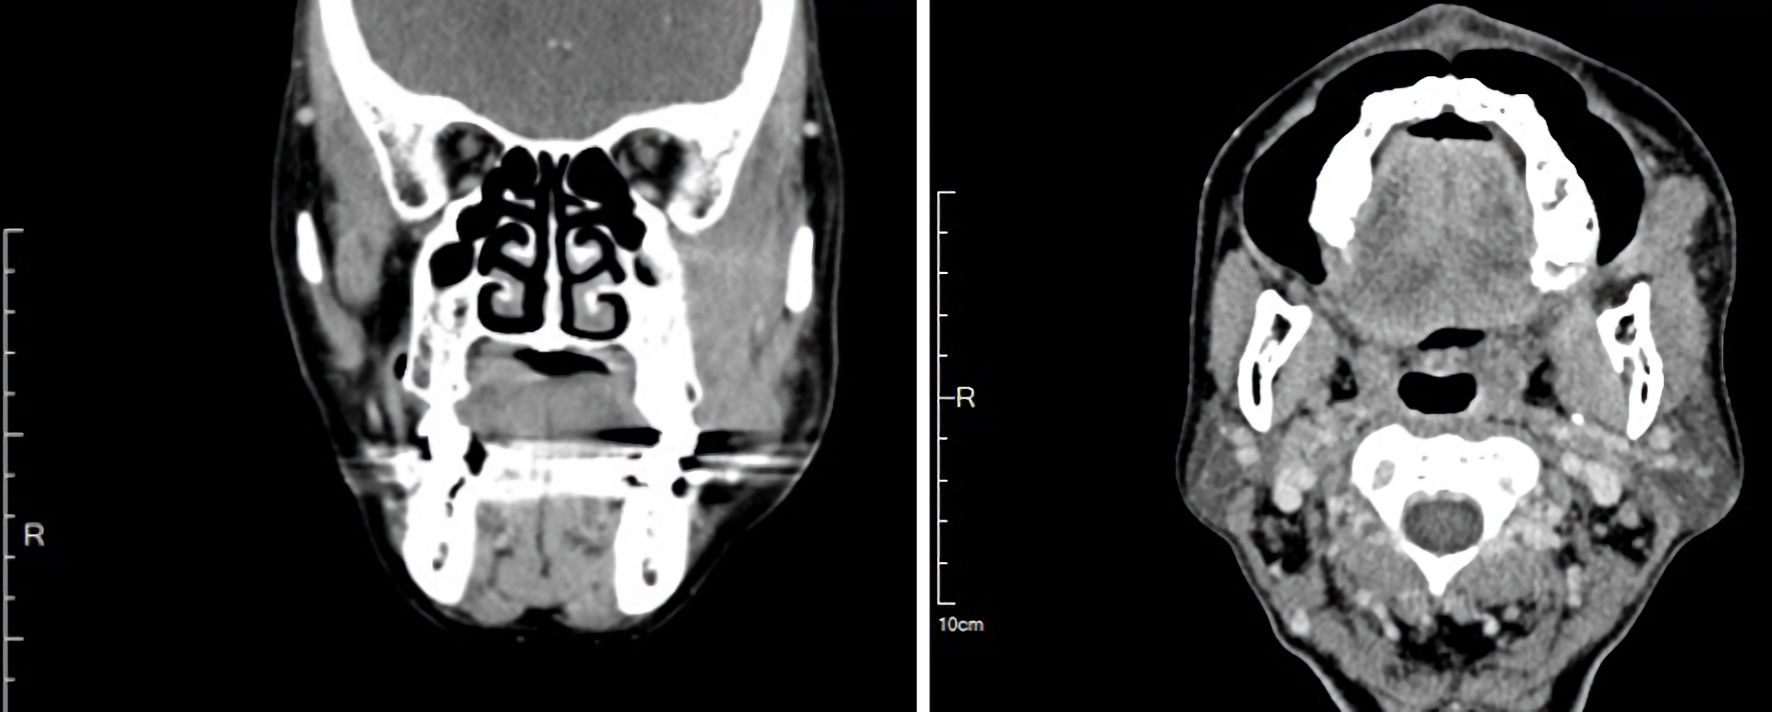

Contrast-enhanced computed tomography (CT) of the face revealed an infiltrative soft-tissue mass measuring 3.1 × 1.5 × 3.5 cm, centered in the left masticator space, with effacement of fat planes between the masseter, pterygoid, and temporalis muscles; there was no cortical erosion (Fig. 2). Given the deep-space location and infiltrative appearance, an intraoral incisional biopsy was performed under general anesthesia (Fig. 3).

Figure 2. Contrast-enhanced computed tomography revealed an infiltrative soft-tissue mass measuring 3.1 × 1.5 × 3.5 cm, centered in the masticator space with effacement of fat planes between the masseter, pterygoid, and temporalis muscles.

The multi-year, painless enlargement of a buccal mass with preserved function aligns with the indolent biology of EMZL and illustrates why lymphoma may be overlooked in deep facial spaces [2, 4]. In the buccal region, the differential diagnosis for a soft, mobile mass spans lipoma, benign peripheral nerve sheath tumor, venous malformation, accessory parotid or minor salivary lesions, nodular fasciitis, metastatic lymphadenopathy, and sarcomas [4, 8]. A pragmatic red flag is progressive enlargement with cross-sectional imaging that depicts an infiltrative soft-tissue process and blurring of normal fat planes but little necrosis or calcification; frank bone erosion is uncommon at presentation in indolent lymphomas [2, 8]. In our patient, the CT finding of fat-plane effacement between the masseter, pterygoid, and temporalis muscles—without cortical breach—favored deep-space pathology and appropriately prompted biopsy rather than excision of a presumed lipoma. The 4-year history of a persistent and slowly progressive swelling in our patient illustrates how easily such indolent lymphomas can be overlooked and mistaken for benign soft tissue lesions in the absence of pain, mucosal change and dental pathology.